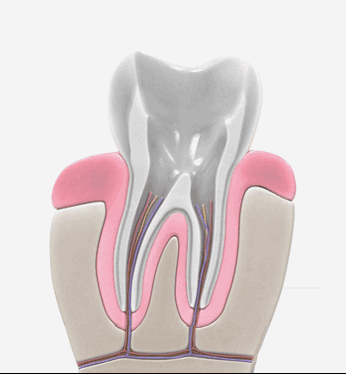

신경치료는 충치가 신경까지 번진 경우, 치아가 부러져 신경이 노출된 경우, 뿌리에 염증이 생긴 경우 진행하는 치료방법입니다. 신경관이 막혀있거나 신경관에 post가 박혀있는 경우 치료의 난이도는 매우 어려워 지며 많은 분들이 발치를 권유 받습니다. 청담뷰치과는 자연치아살리기 진료를 전문적으로 다뤄왔기에 막힌 신경관을 찾거나 만곡이 심한 신경관을 다루는 치료까지 성공적인 결과를 제공해 드릴 수 있습니다.